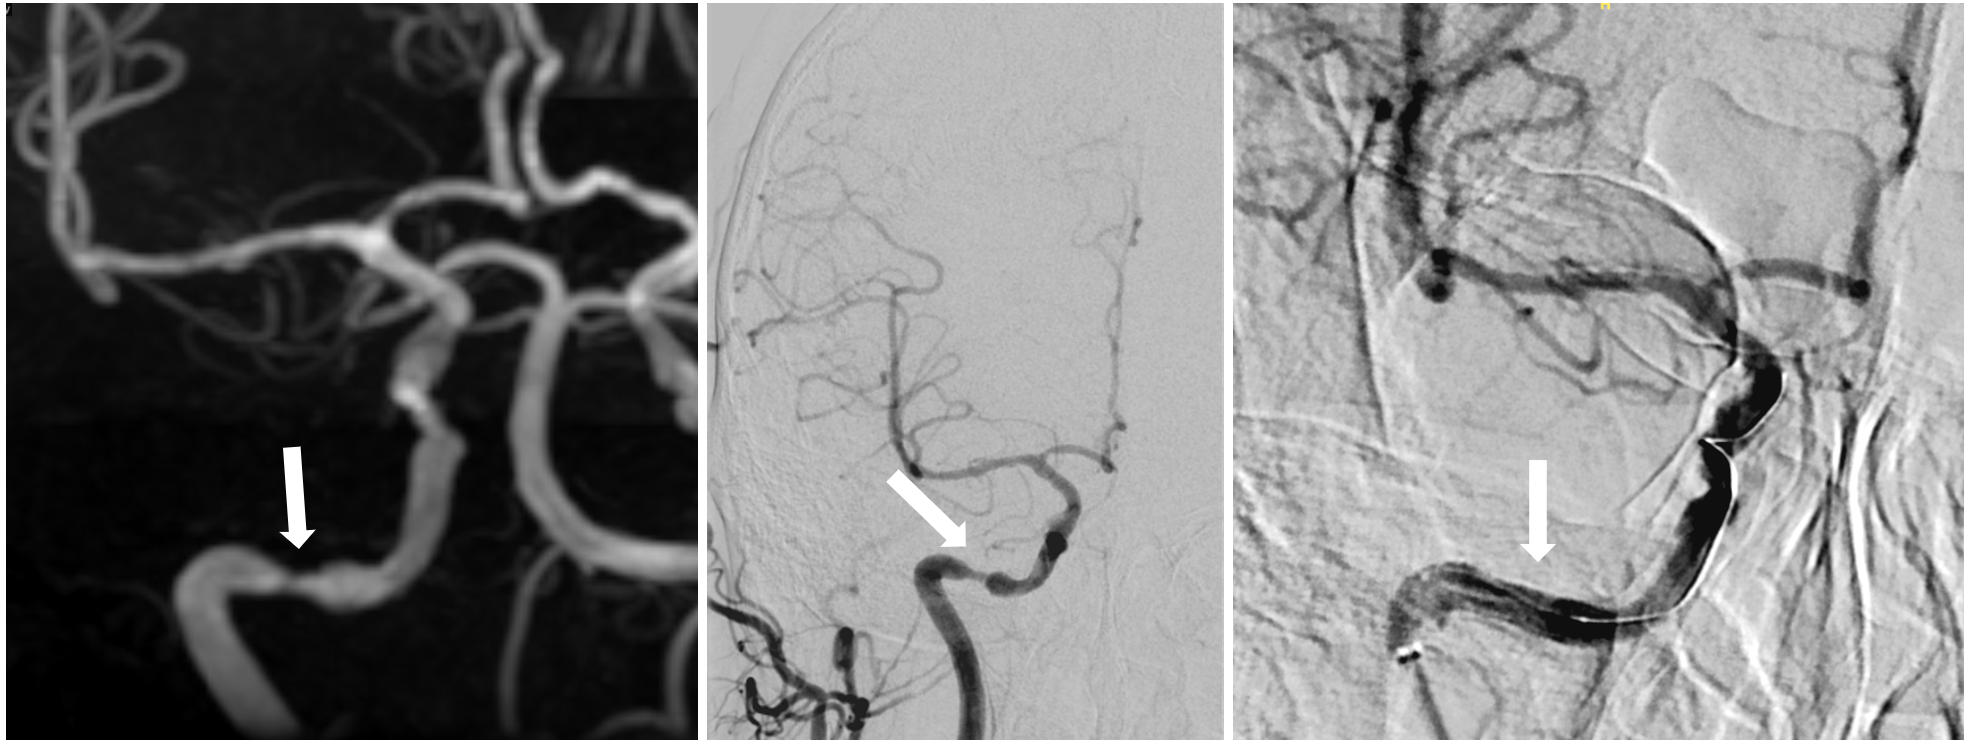

如图可见右侧颈内动脉高颈段重度狭窄,术后通过支架治疗脑血管完全恢复。

为了确保手术的成功,王也副主任医师及其团队在术前做了大量的准备工作。他们会对每一位患者的病情进行全面、细致的评估,结合患者的年龄、身体状况、血管病变程度等多方面因素,制定个性化的手术方案。在手术过程中,他们会运用先进的医疗设备,如颅内高分辨率核磁共振(HR-MRI)和数字减影血管造影(DSA)等,实时监测手术进展,确保每一个操作都准确无误。术后,他们还会对患者进行密切的观察和护理,及时发现并处理可能出现的并发症,为患者的康复提供全方位的保障。